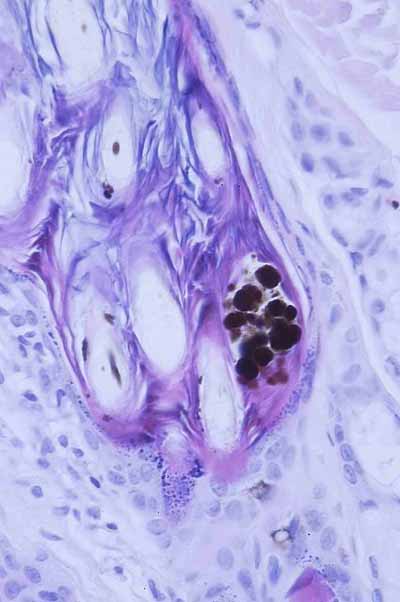

‘’Elles sont avant tout caractérisées par de sévères lésions de pyodermite profonde plus ou moins cicatricielles, stabilisées ou en évolution à type furonculose et d’hydrosadénite rétrograde. On note aussi une dermatose alopéciante avec hyperplasie des structures épithéliales épidermiques et folliculaires, troubles du cycle folliculaire et présence d’anomalies de répartition du pigment mélanique. Présence en outre d’un kyste folliculaire hébergeant des levures du genre malassezia .‘’

Photo 9 DF : Gaine épithéliale externe du follicule pileux hyperplasique (Photo F. Degorce )